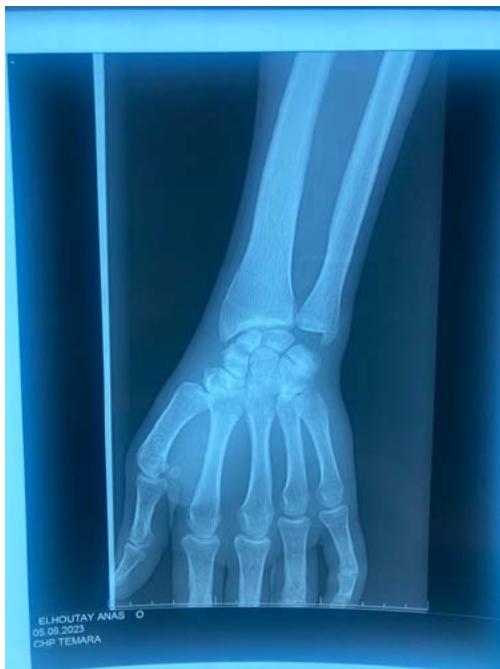

The standard radiographic assessment revealed a scaphoid fracture with an underlying gap, suggesting the possibility of a cyst or pseudarthrosis of the scaphoid (figure 1). The wrist CT scan confirmed the scaphoid fracture with a probable intraosseous cyst (figure 2).

Figure 1: The standard X-ray of the wrist, in frontal and oblique views, revealed a displaced fracture of the scaphoid on a lacunar image located in the middle portion of the scaphoid.